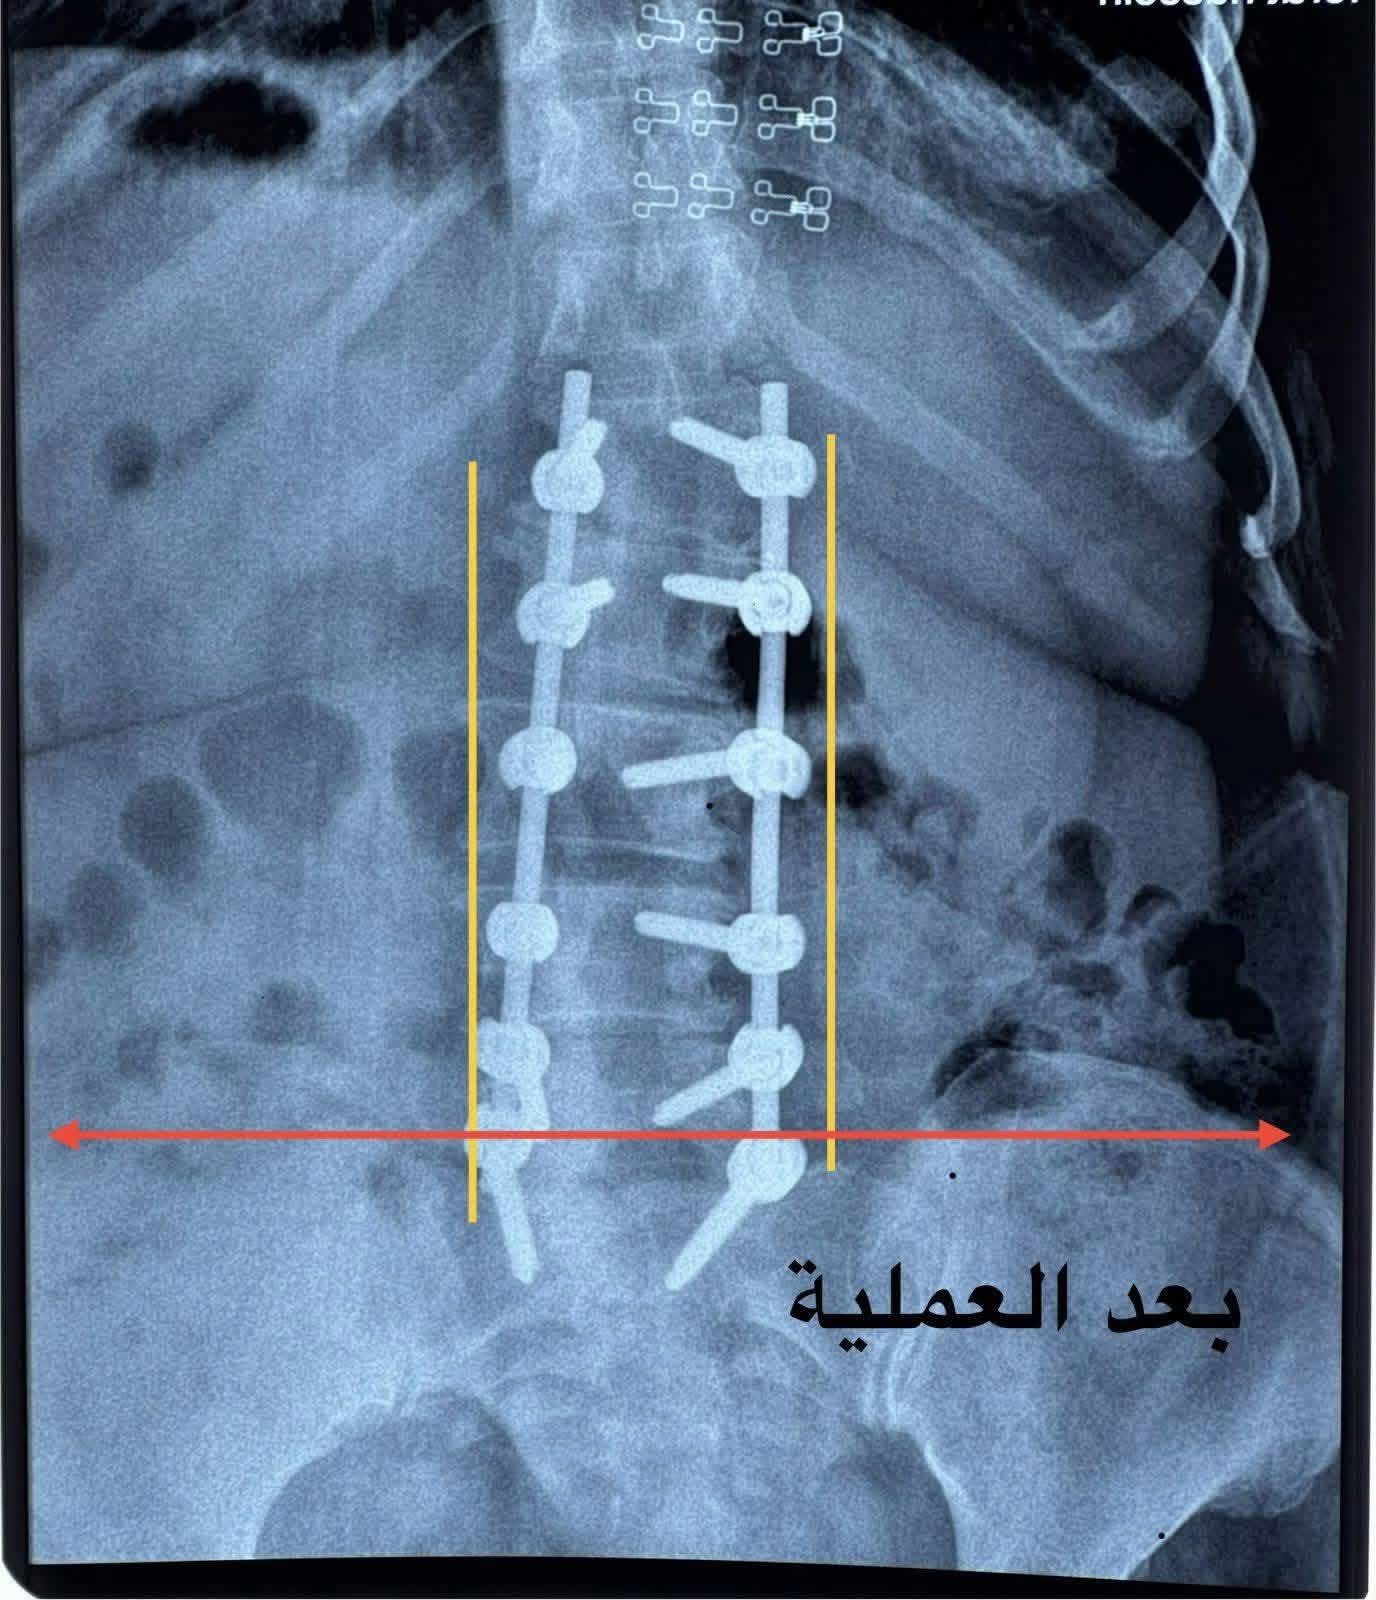

وبيّنت الإدارة أن الفريق الطبي قرر إجراء تداخل جراحي تضمن فتح الفقرات القطنية، وتحرير جذور الأعصاب، وتثبيت الفقرات باستخدام براغٍ وأعمدة من التيتانيوم، مع تعديل الاعوجاج القطني. وقد تكللت العملية بالنجاح، حيث اختفت آلام الظهر والأطراف السفلية لدى المريضة وتحسن الخدر بشكل ملحوظ.